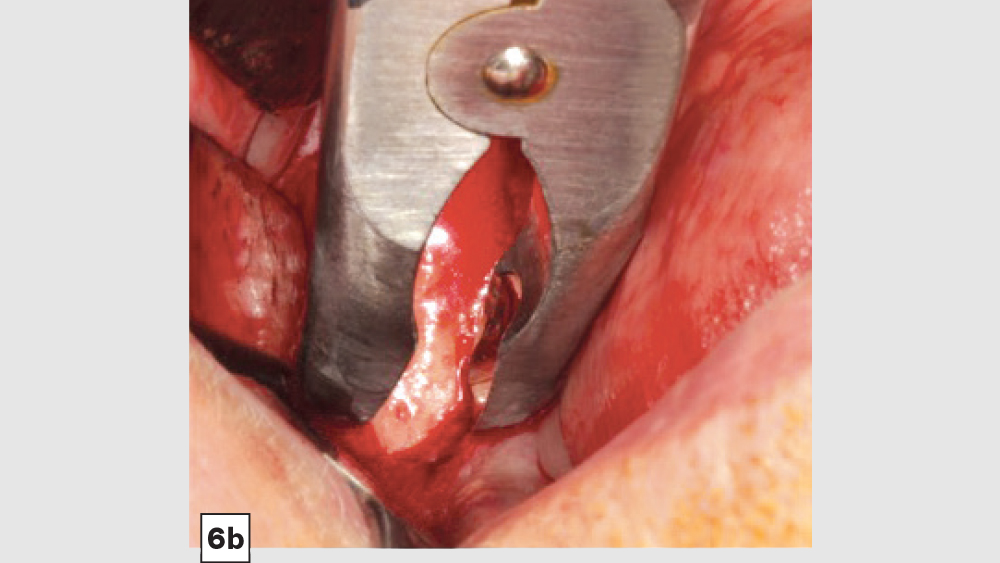

a. Mandibular Ramus Donor Site — The “Scraping Technique”: One option to obtain autogenous bone is to expose the mandibular ramus and remove bone from the external oblique ridge with double-action rongeurs (Figs. 6a, 6b). The “scrapings” may be placed in a surgical bowl with sterile saline. Ramus block grafts may be harvested; however, the blocks need to be reduced into smaller pieces, which is rather time-consuming. Additionally, a ramus block graft (i.e., veneer graft of the lateral ramus) has a higher surgical morbidity and far greater post-op complications.

Figure 6a

Figure 6b

Figures 6a, 6b: Ramus autogenous graft: mandibular ramus exposed (6a), scrapings harvested with double-action rongeurs (6b).